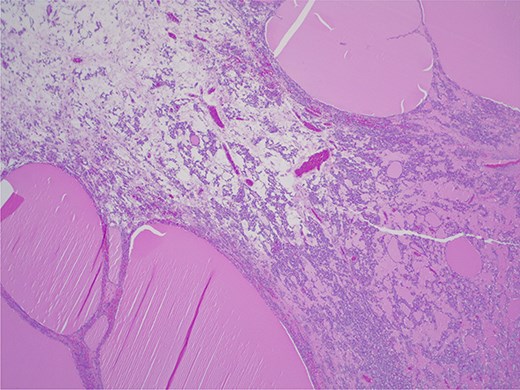

Struma ovarii—thyroid tissue is the dominant component with large and small colloid-containing follicles: H&E ×25.